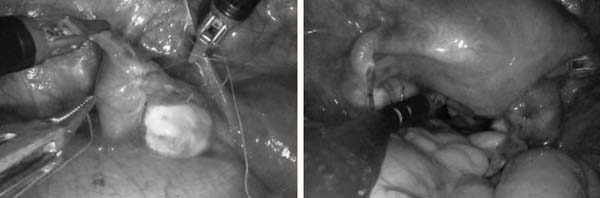

刘薇教授团队进行手术

输卵管精细吻合;美兰试验显示吻合后输卵管通畅